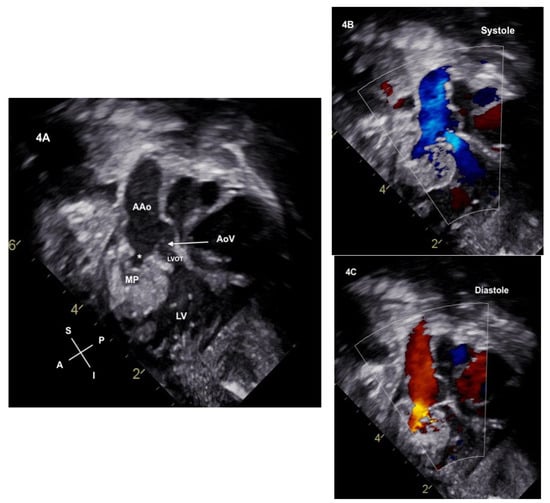

Figure 4.

(A) Neonatal echocardiogram from the subcostal sagittal plane demonstrates the aortic valve (AoV) leaflets (denoted by the arrow) which were not seen on the fetal scans. The aortic valve annulus is hypoplastic with a narrowed left ventricular outflow tract (LVOT). The ruptured sinus connection (*) to the myocardial pouch (MP) is noted. (B) Color is now applied and antegrade flow is noted through the LVOT and into to the ascending aorta. Antegrade flow is also seen from the myocardial pouch into the ascending aorta. (C) Color in diastole demonstrates the reversal of flow from the ascending aorta into the myocardial pouch through the ruptured sinus of Valsalva. Notably, no aortic valve insufficiency is seen when the valve leaflets are closed, and no diastolic flow reversal is noted in the LVOT.